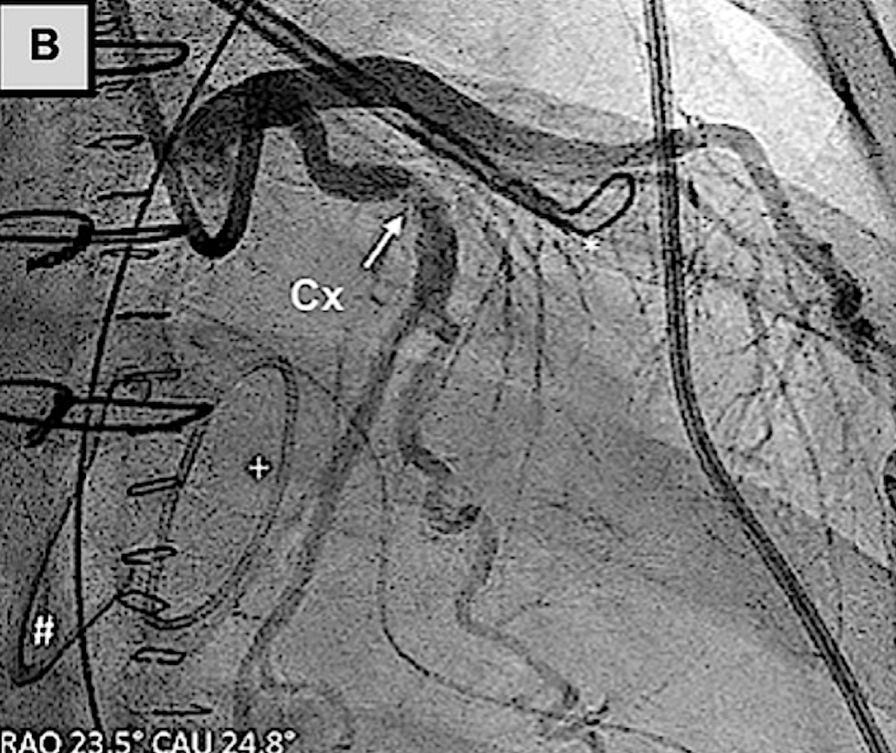

Amplatze左心耳封堵术与左冠状动脉的关系

(A)使用Amplatzer装置的左心耳封堵术已完全展开。冠状动脉造影证实,在植入后,回旋支-M1冠状动脉存在明显狭窄。(B)回旋支-经皮冠状动脉介入治疗

临床病例报告也证实了该损伤的可干预性:一例59岁患者行Amulet装置左心耳封堵时,因装置压迫导致LCX近端重度狭窄,出现下壁ST段抬高,重新将装置深入左心耳开口并联合LCX-PCI后,狭窄完全解除;另一例患者行二尖瓣、三尖瓣手术联合AtriClip装置左心耳封堵后24小时,因装置压迫导致LCX闭塞引发心肌梗死,经LCX-PCI后狭窄显著改善。

因此,外科操作中需将AtriClip装置放置于远离左心耳基底部的位置,避免LCX闭塞。

AtriClip左心耳封堵术与左冠状动脉的关系

(A)术前冠状动脉造影显示回旋支狭窄不显著。(B、C)使用AtriClip装置进行左心耳封堵术后,冠状动脉造影证实回旋支存在显著狭窄。(D)回旋支经皮冠状动脉介入治疗后,冠状动脉造影显示血管造影结果良好